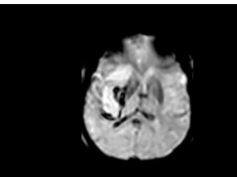

Mechanism of Amyloid Removal in Patients With Alzheimer Disease Treated With Gantenerumab Part 1

- Date : 01/01/2020

Mechanism of Amyloid Removal in Patients With Alzheimer Disease Treated With Gantenerumab Part 3